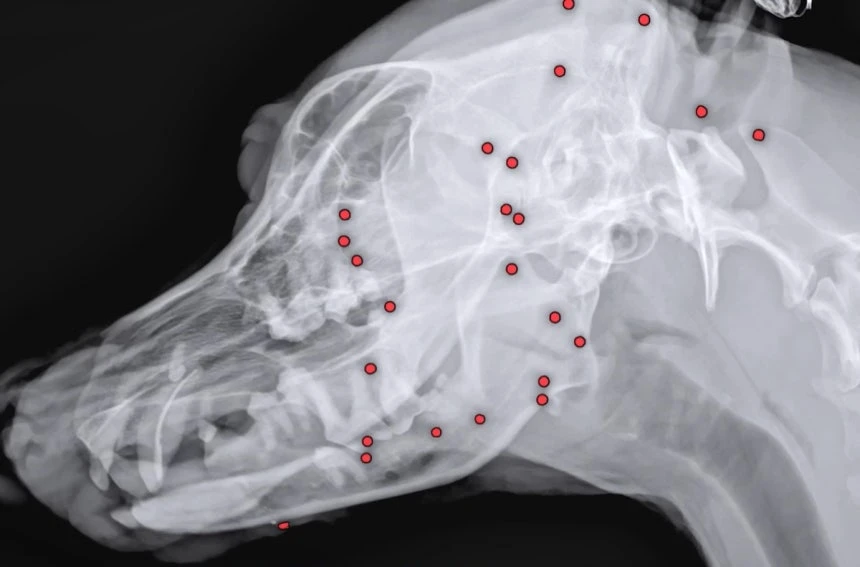

온몸에 총알 70여개가 박힌 채 버려진 백구 사연이 알려지며 공분을 샀다. /사진=VIP동물의료센터 유튜브 화면 캡처

X-레이 촬영 결과 온몸 곳곳에 총알 70여개가 박힌 것으로 확인돼서다. 작은 구슬처럼 보이는 총알이 머리부터 어깨, 가슴, 엉덩이, 다리 등 몸 구석구석에서 발견됐다.

이 모습을 본 안승엽 VIP동물의료센터 원장은 "살아있는 게 기적"이라고 했다.

발견된 총알은 산탄총 파편이었다. 의료진은 정밀 검사를 거쳐 최근 산탄총 파편 제거 수술을 진행했다. 3시간 정도 걸린 수술을 통해 26개의 파편을 제거했다. 모든 파편을 제거하기엔 장기 손상의 위험이 있었다.